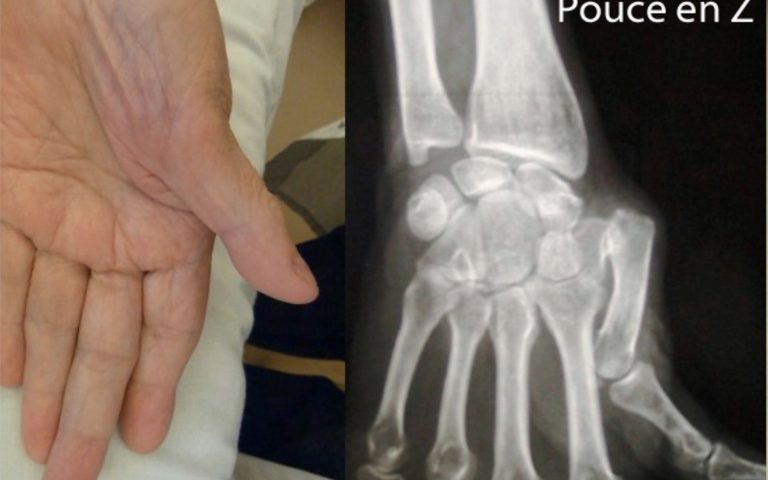

Pathologies de la Main et du poignet Rhizarthrose ou arthrose du pouce

Rhizarthrose ou arthrose du pouce